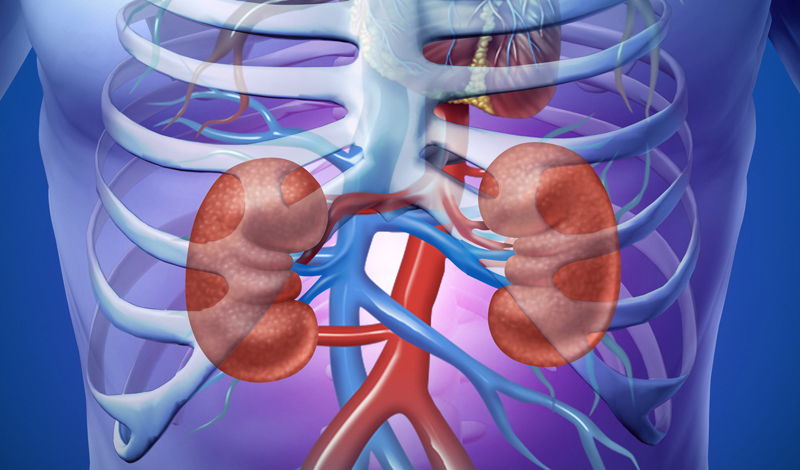

Kidney Biopsy

A kidney biopsy is a diagnostic procedure in which a small sample of kidney tissue is taken and examined